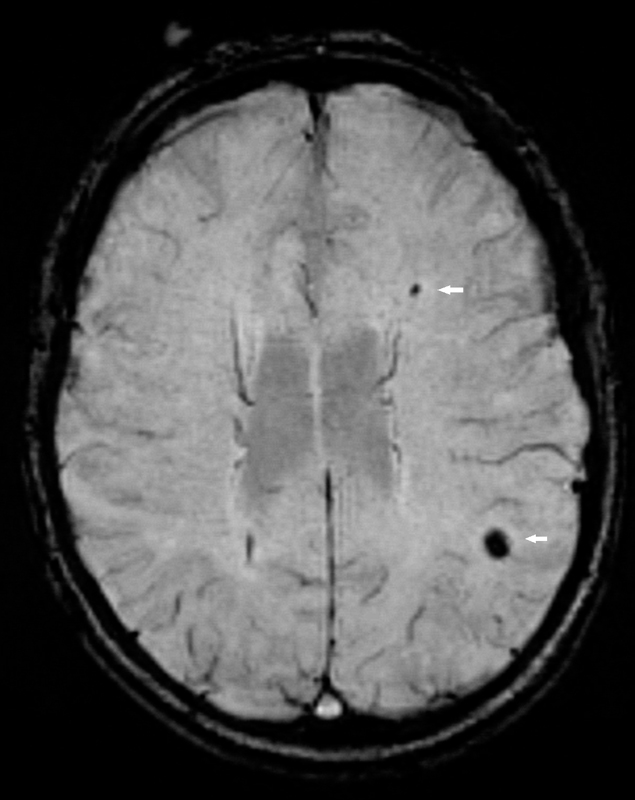

Figure 2 Cerebral microbleeds.

Cerebral microbleeds (arrows) cause susceptibility related signal loss and hence appear dark on susceptibility weighted imaging (SWI).